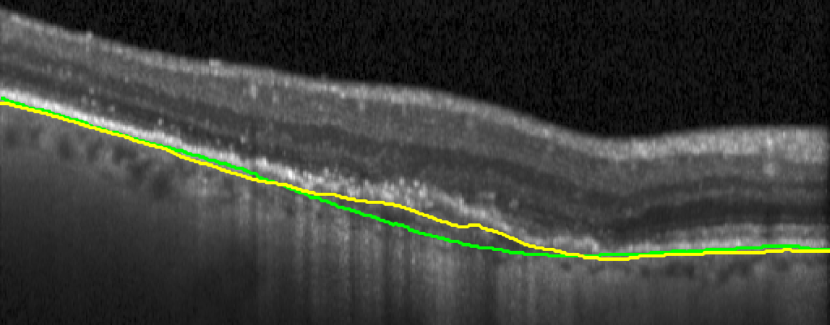

Bruch’s Membrane is an elastic smooth and thin structure, strategically located between the retina and the general circulation, having a crucial role in retinal function, aging and disease [14]. Automated segmentation of the BM is particularly important in the context of AMD as, unlike other common retinal diseases such as DR, RVO, or glaucoma, the BM is distinguishable from the outer RPE boundary. In specific, drusen in iAMD and PEDs in nAMD separate the RPE from BM, requiring the segmentation of the region in-between them. In addition, in case of GA, the RPE is completely lost in some locations, exposing only the BM, thus imposing additional difficulties for algorithms and calculations that depend on the RPE position. Achieving correct automated identification of the BM is challenging in many cases, mainly due to the small thickness of this layer, the high reflectivity of the RPE that shadows parts of the BM, and the noise being present in the scans, which is often indistinguishable from the content of drusen and PEDs (Fig. 4). Due to these difficulties, currently many automated solutions either do not provide a segmentation of the BM or its segmentation is often inaccurate in retinal OCT with AMD, leaving this clinically relevant segmentation task unaddressed or under-explored.

(a) iAMD

(b) nAMD

(c) GA